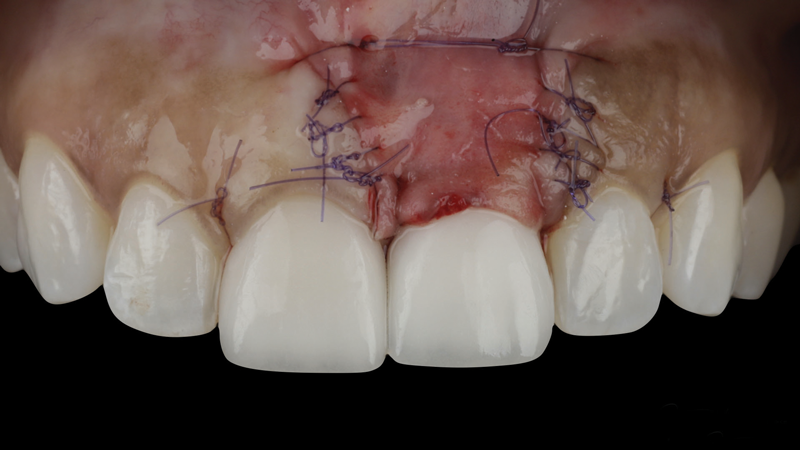

(8.) The flap was coronally positioned and sutured into place.

Figure 8